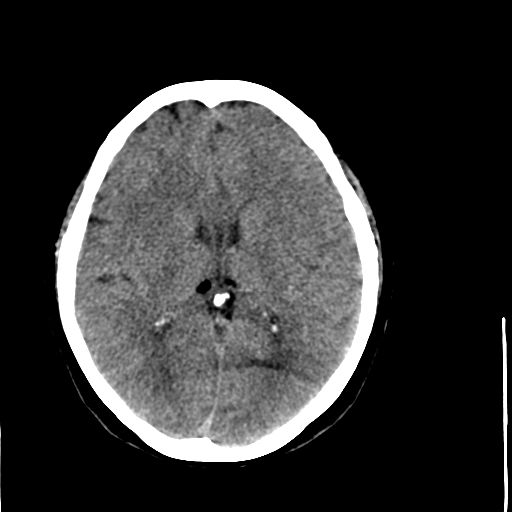

病人资料:女,57岁,反复头痛6年余,无恶心、呕吐等症状,体查:bp180/100mmhg。

脂肪瘤

脂肪瘤。

颅内脂肪瘤

中线脂肪瘤

胼胝体发育不良并脂肪瘤形成,脂肪瘤形成是因,胼胝体发育不良是果。如果正规些应该是中线脂肪瘤并胼胝体发育不良!

典型中线脂肪瘤

胼胝体发育不良

中线脂肪瘤并胼胝体发育不良。